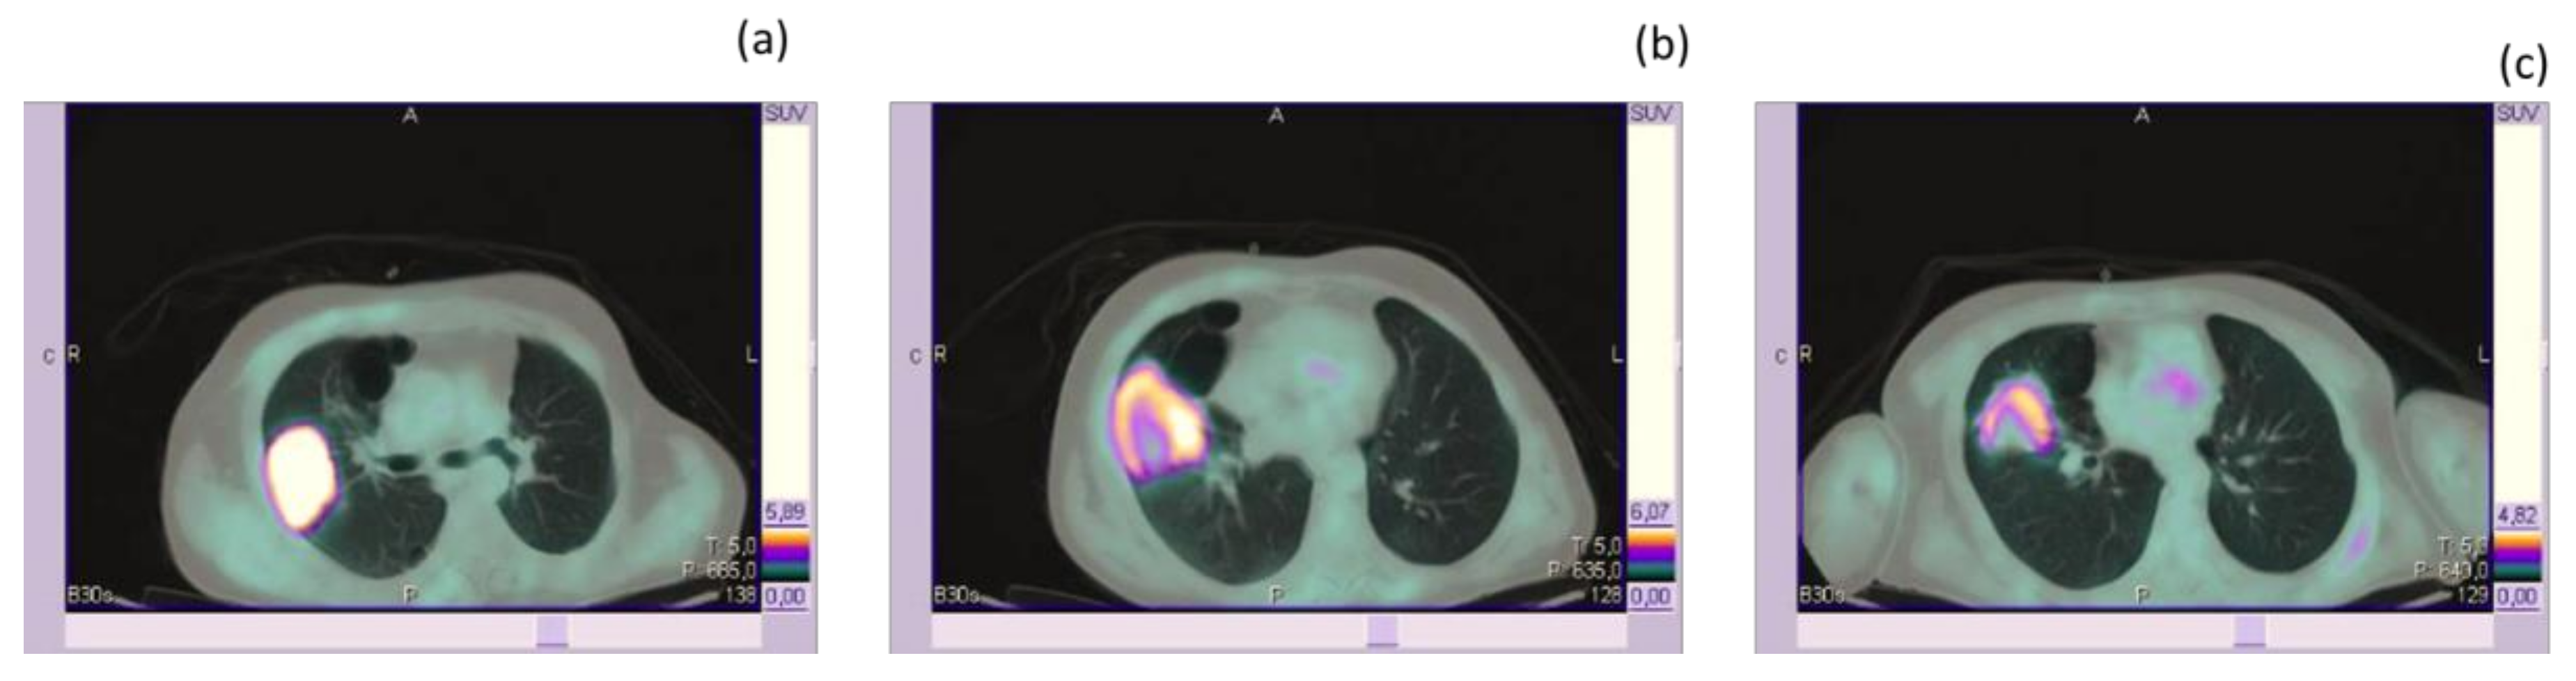

- Iravani, A.; Osman, M.M.; Weppler, A.M.; Wallace, R.; Galligan, A.; Lasocki, A.; Hunter, M.O.; Akhurst, T.; Hofman, M.S.; Lau, P.; et al. FDG PET/CT for tumoral and systemic immune response monitoring of advanced melanoma during first-line combination ipilimumab and nivolumab treatment. Eur. J. Nucl. Med. Mol. Imaging 2020. [Google Scholar] [CrossRef]

| Iravani et al. [66] | retrospective | 31 patients who had first-line nivolumab plus ipilimumab; pre- and post-treatment [18F]FDG PET/CT scans within 2 and 4 months of starting ICI, respectively and at least one lesion assessable by PERCIST. | To investigate the role of [18F]FDG PET/CT in monitoring of response and immune-related adverse events following first-line combination-ICI therapy for advanced melanoma. | Outcomes in patients who had first-line nivolumab plus ipilimumab were reviewed; pre- and post-treatment FDG-PET/CT scans within 2 and 4 months of starting ICI, respectively; and at least one lesion assessable by PERCIST. | The best-overall responses were CMR in 25 (80%), PMR in 3 (10%), and PMD in 3 (10%) patients. Patients with PMD had significantly higher pre-treatment wbMTV (p = 0.009). Secondary progression The most common [18F]FDG PET/CT detectable immune-related adverse event were endocrinopathies and enterocolitis. | [18F]FDG PET/CT response evaluation predicts the long-term outcome of patients treated with first-line combination-ICIs.. Beyond response assessment, [18F]FDG PET/CT frequently detects clinically relevant irAEs. |